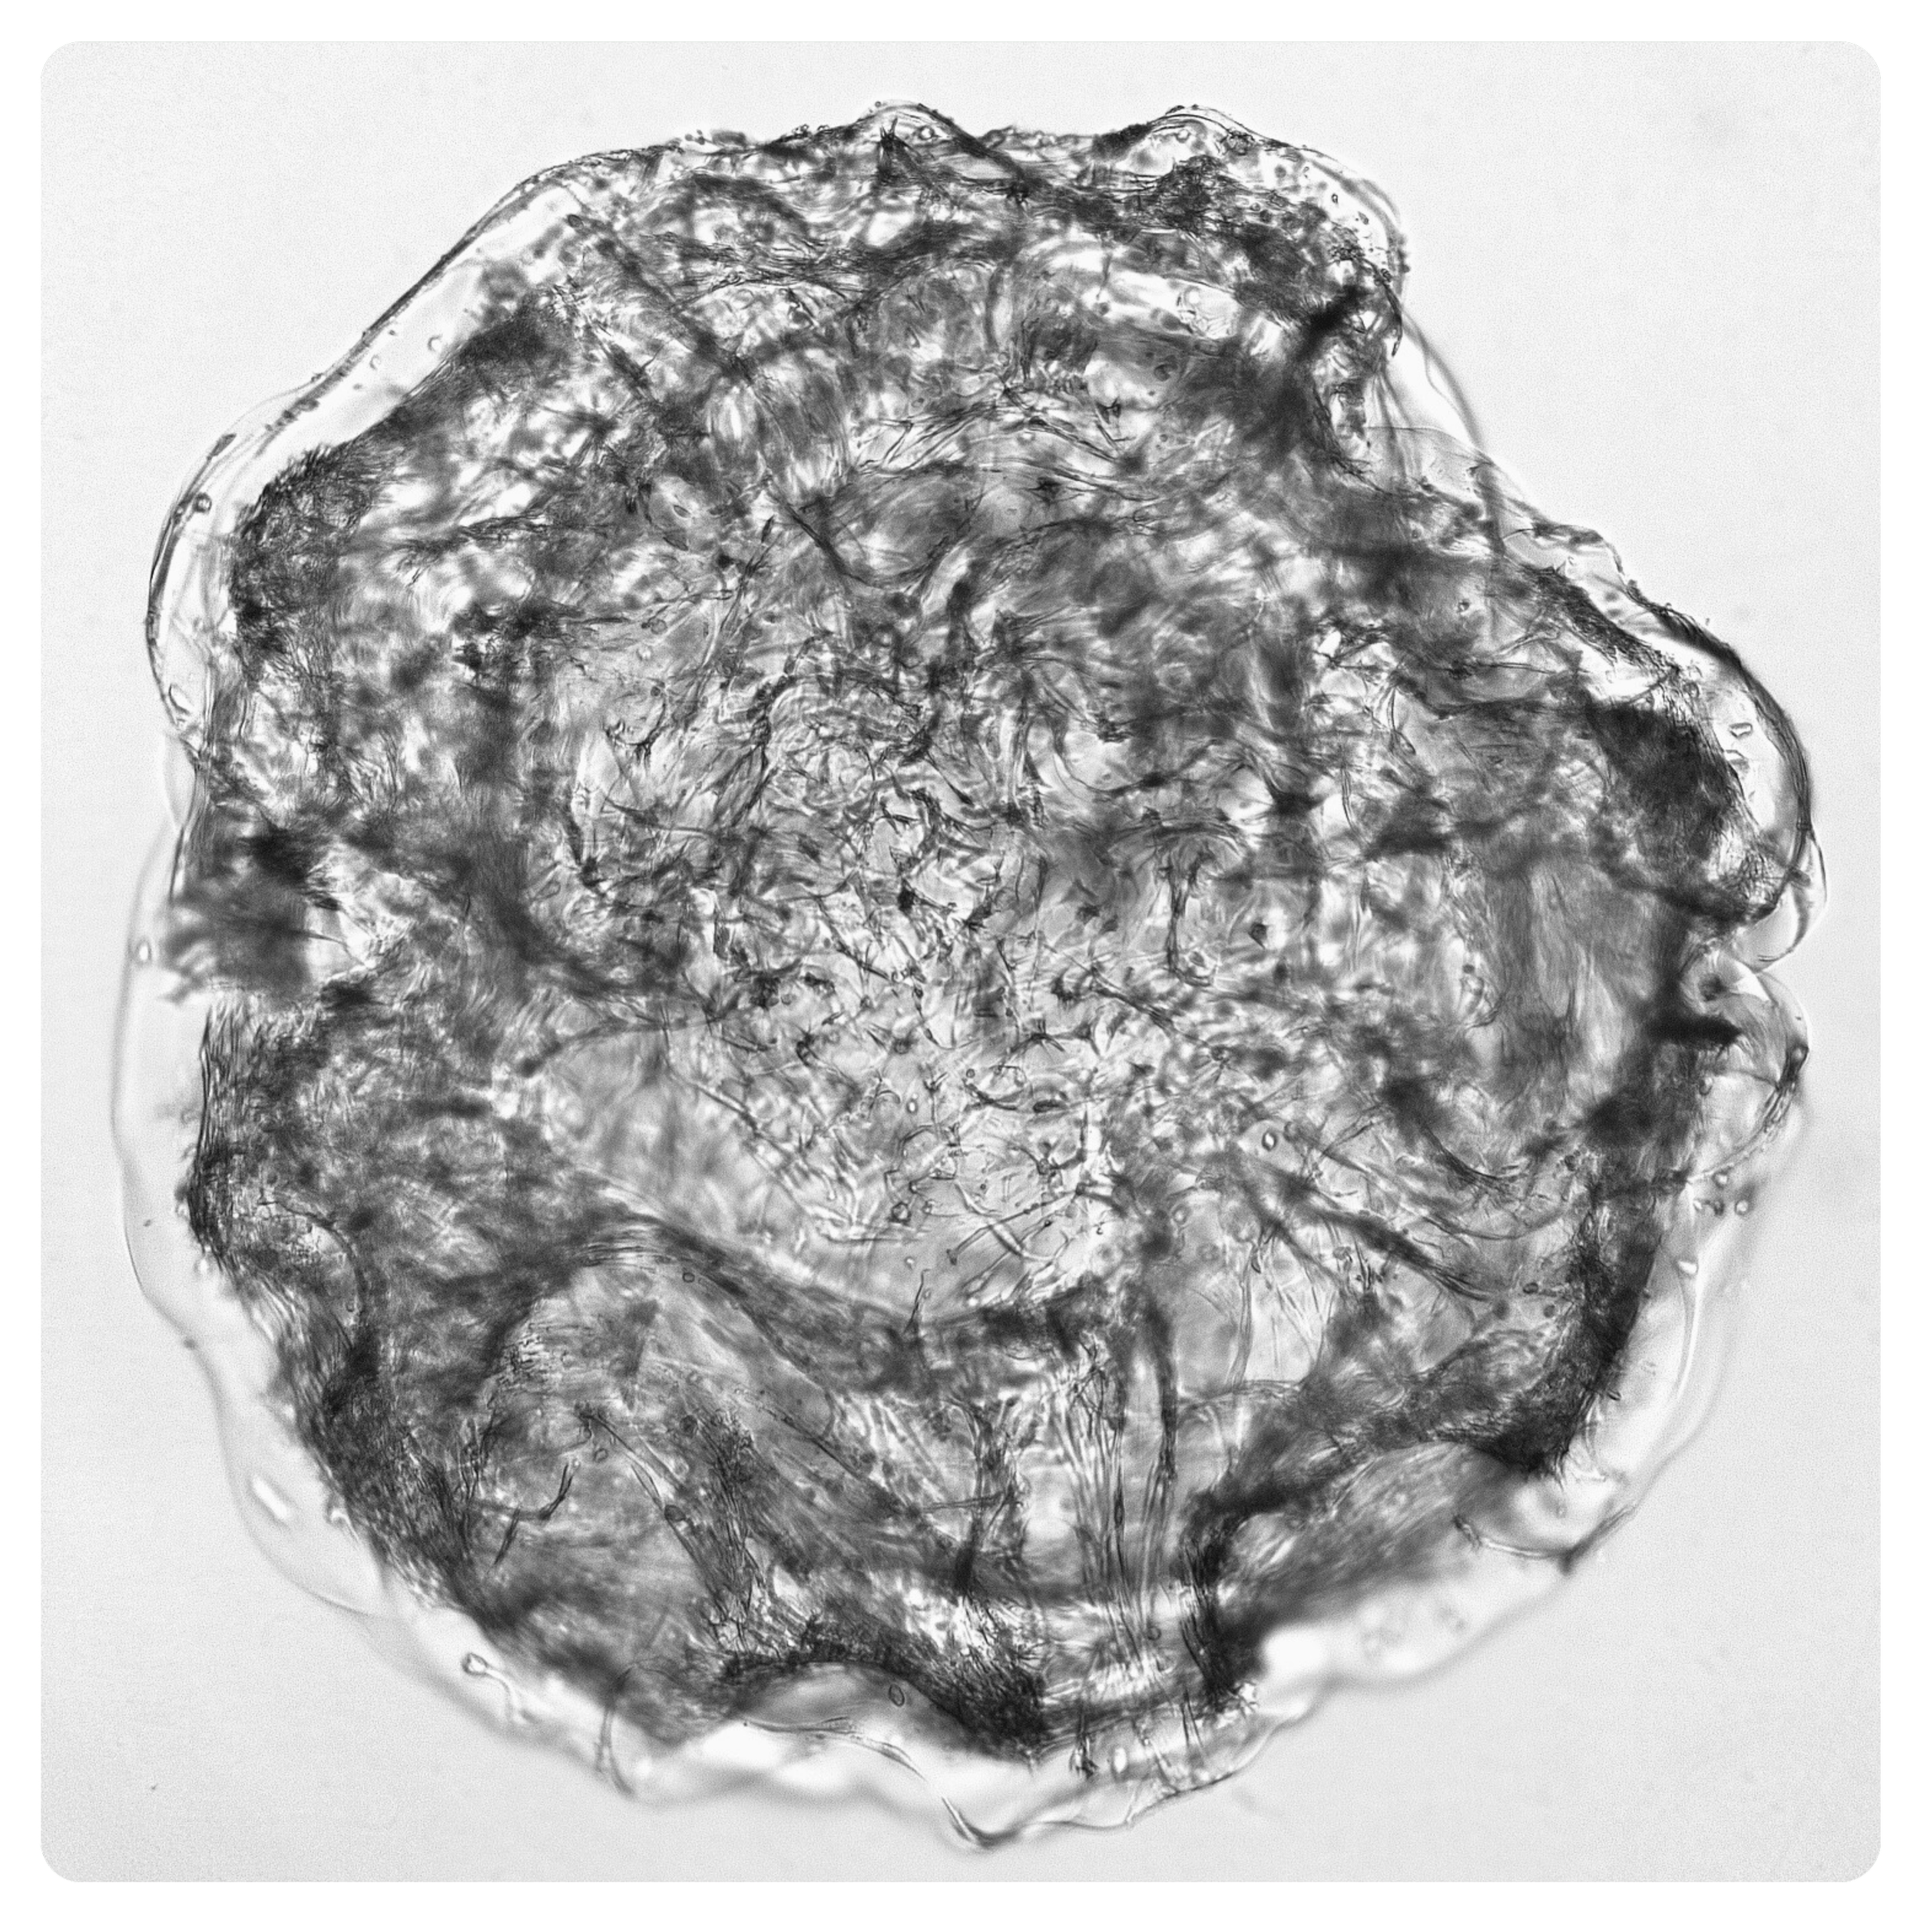

ArtiBrain™ brightfield image

Derived from human iPSCs, ArtiBrain™ provides a physiologically relevant model of the healthy brain. Within just three weeks, human neural stem cells give rise to multiple brain cells that self-organise to form dense synaptic networks embedded in their own secreted ECM — ready for drug discovery.

Dense synaptic connectivity matured in ~21 days — rapid time-to-data compared with variable organoids.